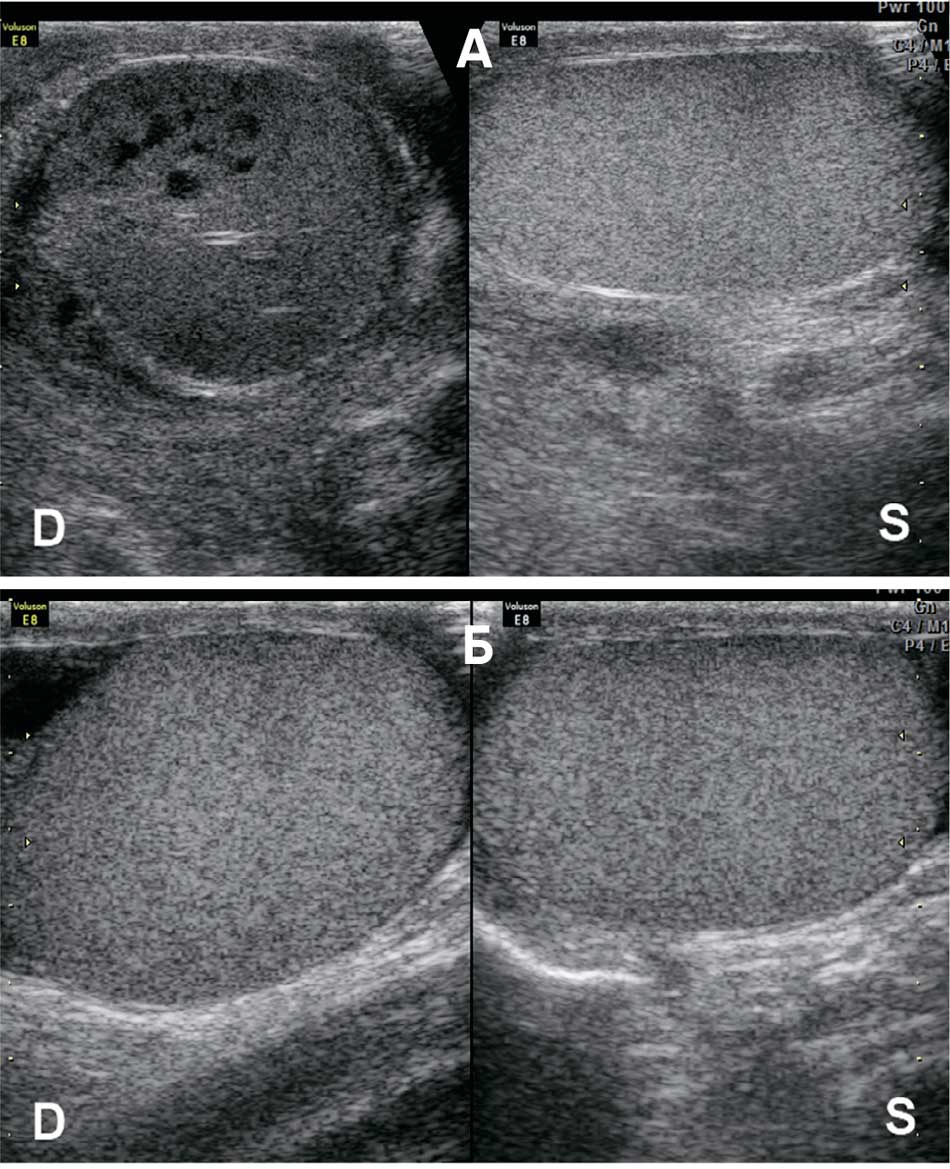

Рис. 4. Варианты эхографической визуализации перекрученных яичек:

D – правое яичко; S – левое яичко

а – перекрут правого яичка: паренхима структурна, яичко перспективно для деторсии;

б – перекрут правого яичка: паренхима неструктурна, яичко не перспективно для деторсии

Fig. 4. Options for echographic visualization of twisted testicles:

D – right testicle; S – left testicle

a – torsion of the right testicle: parenchyma is structural, testicle is amenable to detorsion;

b – torsion of the right testicle: parenchyma is not structural, testicle is not amenable to detorsion